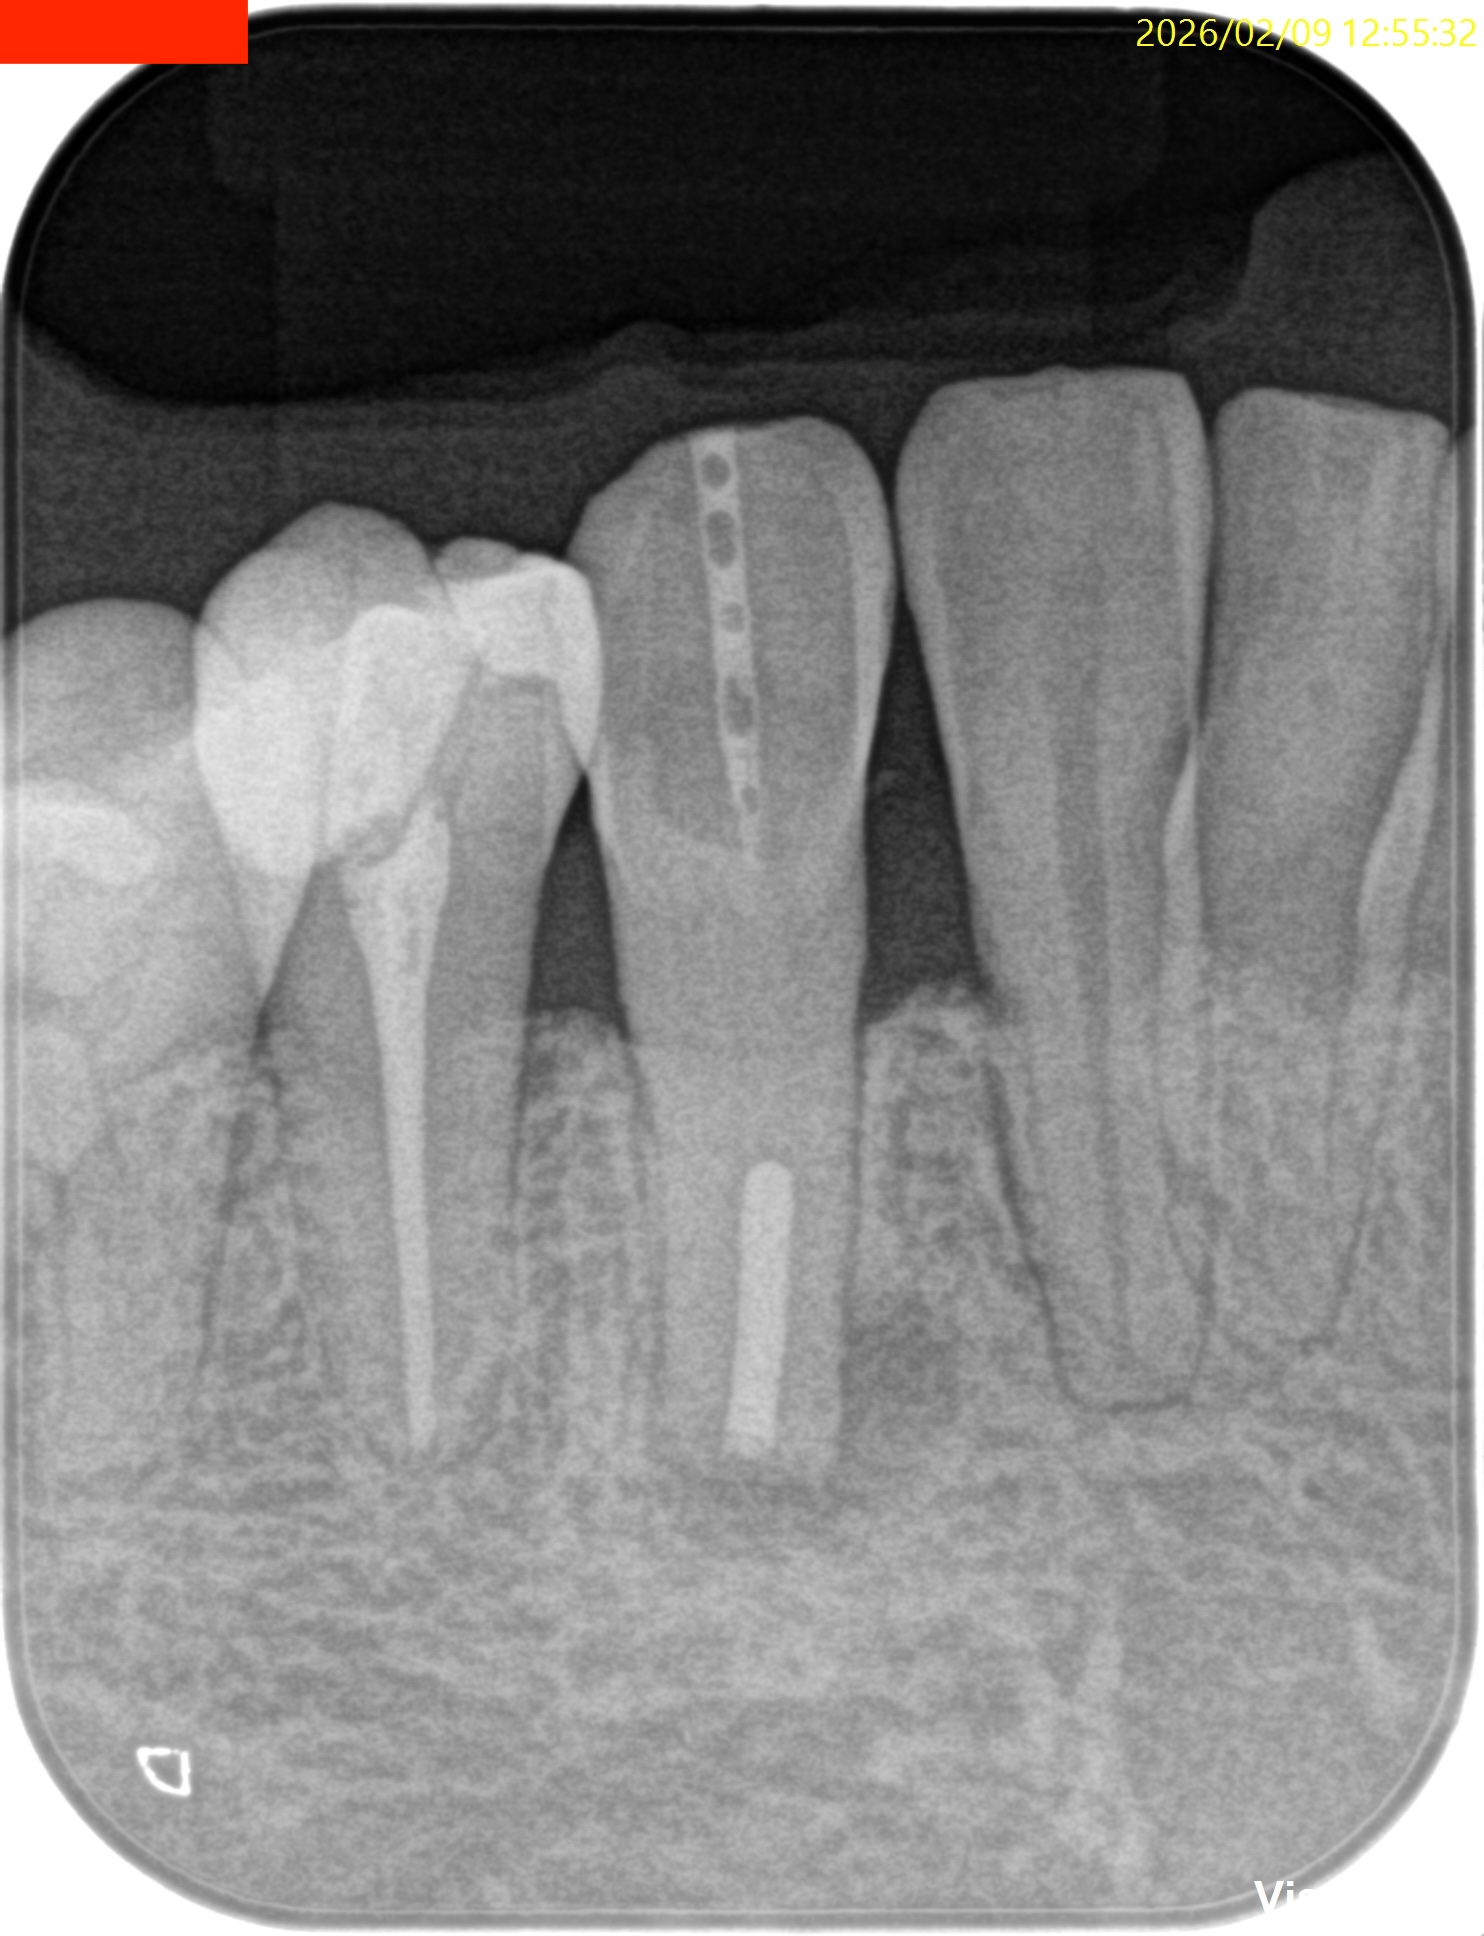

#27 RCT(2026.2.9)

根管治療だがCBCTによれば、

切端からApexまで約25mmだ。

切端を削れば露髄するはず?である。

が、根管は硬かった…。。。

ということで窩洞をレジンで充填し、Intentional Replantationへ移行した。

#27 Intentional Replantation(2026.2.9)

PAを撮影した。

問題はないだろう。